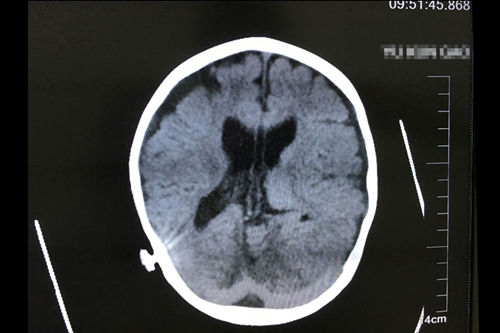

亮亮正式出院三个月后复查CT影像显示:慢性中度以上阻塞性脑积水,脑室分流术后改变

前不久,爸爸妈妈又带着正式出院三个月的亮亮前来复诊,检查结果显示亮亮头部的创伤正在痊愈,大脑在正常发育。亮亮见了医生、护士、护工就像见到了亲人,大家亲切地和亮亮打着招呼,抱他、哄他、逗他开心,还专门买了水果和零食送给他吃。经过侯增欣主任的复查之后,爸爸开心地说:“再康复休养两年,亮亮差不多就可以回学校上学了。”